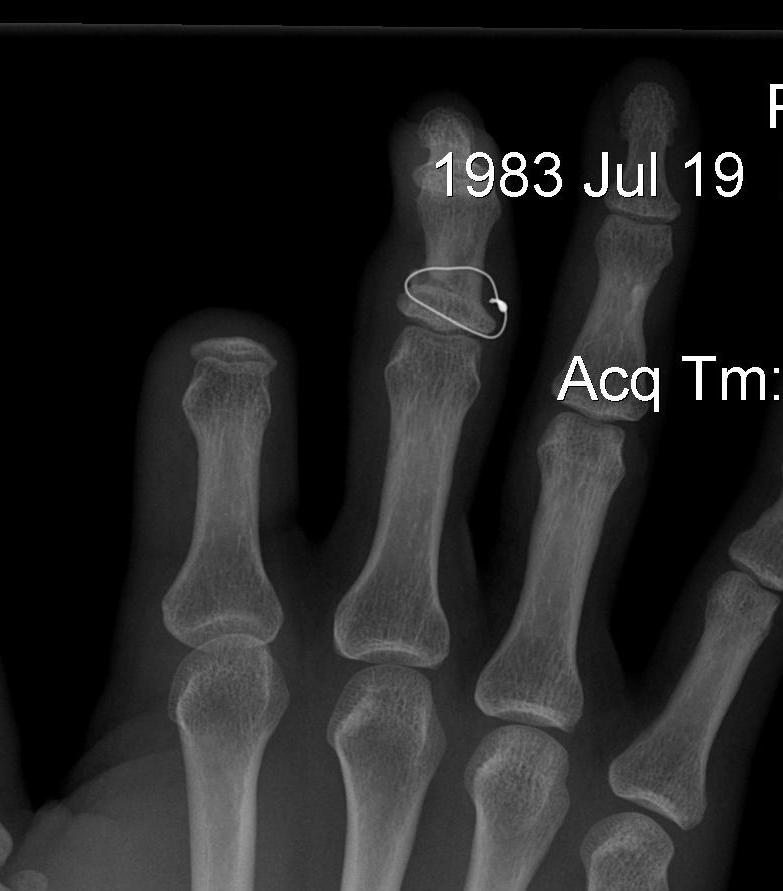

![]()

Displaced unicondylar

- percutaneous K wire

- ORIF with screw